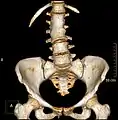

Congenital block vertebra of the lumbar spine. CT volume rendering.